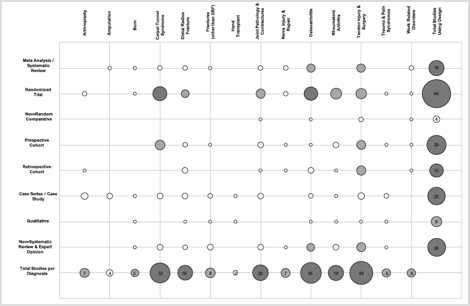

对于 36 种手部和手腕状况治疗组合,四种常用的患者报告结果测量的最重要变化是什么

文章审稿人:Case Peters Reference Hoogendam, L.、Koopman, JE、van Kooj, YE、Feitz, R.、Hundepool, CA、Zhou, C. ... 腕部研究小组 ...